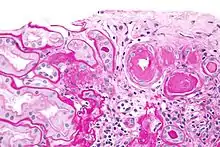

Гіаліноз — різновид білкової дистрофії, при якій в тканинах відкладаються гомогенні, напівпрозорі, щільні маси — гіалін. До складу гіаліну входять білки плазми крові, ліпіди, мукополісахариди.[1]

Гіаліноз спостерігається в сполучній тканині, стромі органів, в стінках судин, що призводить до їх ущільнення. Найбільше клінічне значення має системний гіаліноз сполучної тканини (див. Колагенові хвороби) і судин. Місцевий гіаліноз пов'язаний з місцевими обмінними порушеннями в тканини і частіше спостерігається в рубцях, спайках, вогнищі хронічного запалення, у великих судинах при атеросклерозі, в осередках змертвіння тканин, пухлинах або як фізіологічне вікове явище в судинах селезінки, підшлункової залози, яєчниках, молочній залозі. Системний гіаліноз незворотній. У деяких випадках місцевого гіалінозу спостерігаються явища розсмоктування.